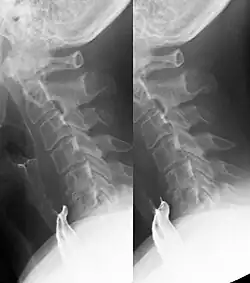

Zervikaler Ösophaguspouch in der Breischluckuntersuchung.

Ein zervikaler ösophagealer Pouch ist eine vorübergehende kleine Ausstülpung der Speiseröhre während des Schluckens am häufigsten nach hinten unmittelbar unter dem oberen Ösophagussphinkter im Laimer-Dreieck. Wenn die Ausstülpung auch in der Ruhephase zwischen dem Schlucken konstant nachweisbar ist, handelt es sich um ein Killian-Jamieson-Divertikel.

Die Lage unter dem Sphinkter und dadurch bedingt die Entleerung nach unten in die Speiseröhre helfen bei der Abgrenzung gegen Zenker-Divertikel und -pouches.